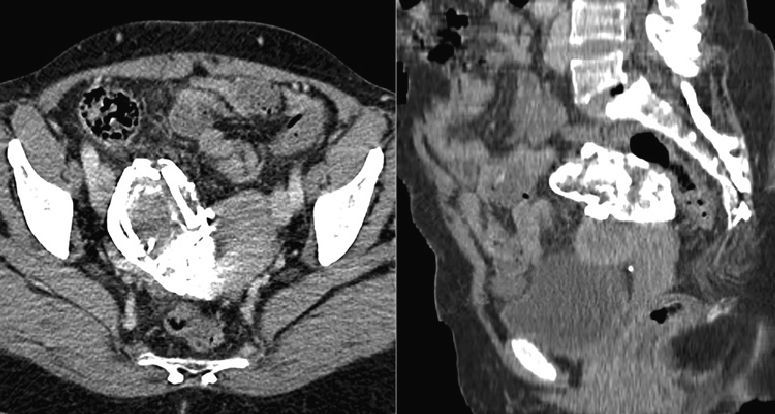

A 48-year-old woman, who had had a previous right ectopic pregnancy that was operated on 25 years earlier, came to our hospital due to coxalgia. Radiography (Fig. 1) identified a calcified hypogastric mass. CT was performed due to suspected calcified uterine fibroid, teratoma, hydatid cyst or textiloma. A calcified tumor was detected that measured 9.5cm×5.2cm adjacent to the upper right side of the uterus (Fig. 2). On the bone window setting, the mass was seen to be a fetal skeleton that was at approximately 24 weeks of gestation (Fig. 3), compatible with lithopedion from an extrauterine pregnancy.